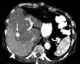

Liver tumor embolization

Liver cancer (also known as hepatic cancer, primary hepatic cancer, or primary hepatic malignancy) is cancer that starts in the liver. The word "hepatic" is from the Greek hêpar, meaning "liver". [Source: Wikipedia ]